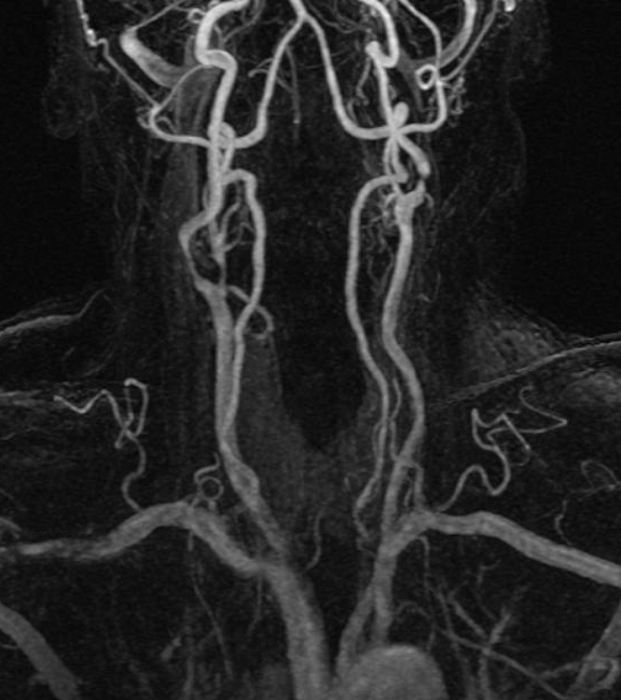

МР бесконтрастная ангиография сосудов шеи

МР бесконтрастная ангиография сосудов шеи – важный метод исследования, который позволяет оценить состояние сосудов шеи.